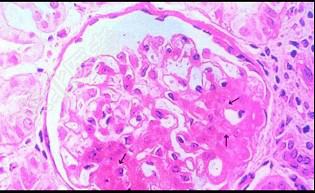

- 单项选择题图-1为HE染色,图-2为PAS染色, 图-3免疫荧光镜下可见IgM团块状沉积于病灶区,图-4电镜下可见上皮细胞足突广泛融合, 系膜增生(M)。阅读这些病理图片,诊断其病理类型是 ( )

A、系膜增生性肾小球肾炎

B、膜增生性肾小球肾炎

C、局灶性节段性肾小球硬化

D、肾小球轻微病变

E、局灶性肾炎